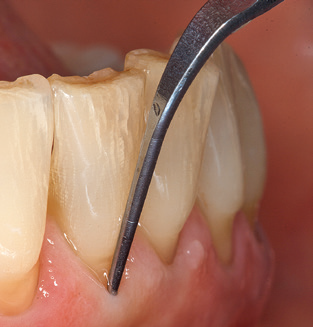

Als zentraler Bestandteil der UPT ist natürlich die Instrumentierung zum mechanischen Entfernen des Biofilms von vorrangiger Bedeutung. Der Ablaufplan einer UPT sieht zu diesem Zweck eine supra, ggf. auch eine subgingivale Reinigung vor. Hier hat sich im Rahmen unseres Konzepts eine Kombination von Handinstrumenten und maschineller Reinigung bewährt. Für die maschinelle Vorgehensweise gibt es mehrere Optionen: Schallgeräte, Ultraschallgeräte sowie Pulverstrahlgeräte.

Die gute Ausleuchtung des Arbeitsfeldes stellt eine wesentliche Erleichterung dar. Bei dem von den Autoren genutzten System ist dies gelungen, indem ein 5facher LEDRing in das Handstück integriert wurde. Natürlich werden für dieses System unterschiedliche Arbeitsspitzen für die jeweiligen Indikationsbereiche angeboten. Eine gerade, universell einsetzbare Spitze ist das Basisinstrument zur maschinellen Instrumentierung natürlicher Zähne (Abb. 5a und b). Für schwer zugängliche Bereiche im Seitenzahnbereich werden gebogene Spitzen angeboten, die auch einen Zugang zu freiliegenden Furkationen ermöglichen (Abb. 6).

Unerlässlich für die UPT implantat prothetisch versorgter Patienten sind natürlich Arbeitsspitzen für die Reinigung von Implantatoberflächen. Der Implantatreinigungsaufsatz des hier verwendeten Systems zeichnet sich dabei durch eine spitz zulaufende sechskantige konische Form aus. Dieses Design erlaubt ein leichtes atraumatisches Eindringen in die periimplantäre Tasche und zeigt eine gute Reinigungsleistung (Abb. 7).

Im Rahmen des gesammelten Patientenfeedbacks stellte sich heraus, dass das System darüber hinaus auch zwei Punkte bietet, die den Patientenkomfort steigern. Dies ist zum einem das Vorwärmen der Spülflüssigkeit, die auch beim Reinigen empfindlicher Zahnoberflächen eine Reizung vermeidet, und der sogenannte Smooth Mode des Systems. Bei diesem Modus verringert sich die Leistung des Systems, je stärker die Spitze an den Zahn gedrückt wird. Diese beiden Aspekte führen dazu, dass die Patienten die Behandlung angenehmer finden als mit früher verwendeten Ultraschallsystemen.

Nach der maschinellen Reinigung der Zahn und Implantatoberflächen erfolgt eine manuelle Instrumentierung der natürlichen Zahnoberflächen mit konventionellen Handinstrumenten. Bei der manuellen Reinigung ist insbesondere auf einen korrekten Anstellwinkel, eine ausreichende Schärfe, eine gute Abstützung und auf eine von apikal nach koronal gerichtete Arbeitsweise der Kürette zu achten. Zur Nachinstrumentierung der Implantatkonstruktionen sollten entweder Titan oder Carbonküretten verwendet werden (Abb. 8). Ergänzend zum Einsatz von Ultraschallgeräten können in der Erhaltungstherapie auch Pulverstrahlgeräte genutzt werden. Dabei ist jedoch zu berücksichtigen, dass diese Verfahren nicht zum Entfernen harter Beläge geeignet sind und daher die Verwendung von Hand oder Ultraschallinstrumenten nicht komplett ersetzen können. Abschließend erfolgt in jedem Fall eine mechanische Politur der zugänglichen Zahn und Implantatoberflächen mit Polierkelchen und Polierpasten (Abb. 9).